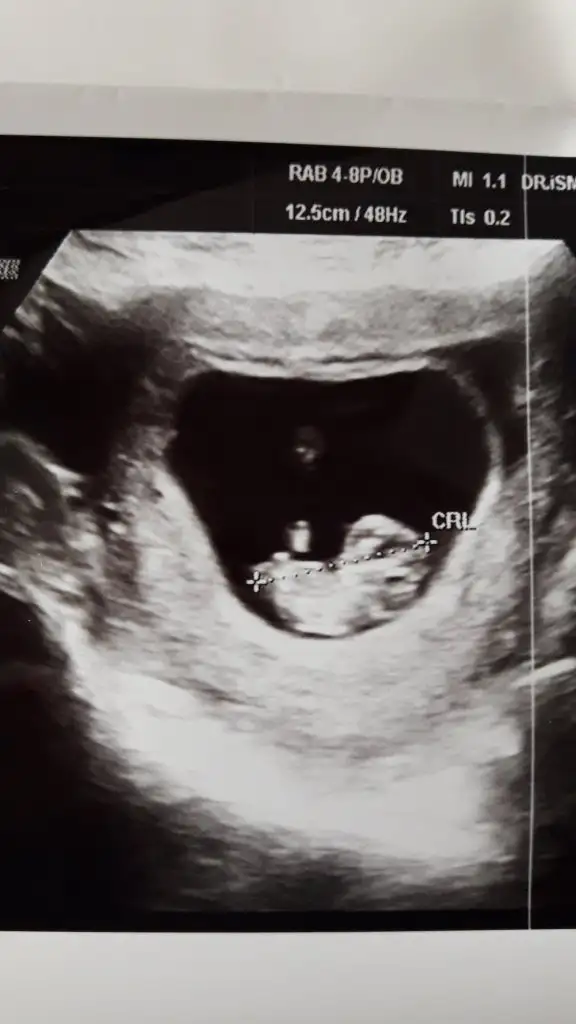

Kız gibi tam net degil 12 hafta usg de paylaşın bir dakineİyi pazarlarbende bir tahmin alabilir miyim acaba ? 10 hafta 5 günlük usg görüntüsü eklediğim.

Kiz gibi net degilİyi pazarlarbende bir tahmin alabilir miyim acaba ? 10 hafta 5 günlük usg görüntüsü eklediğim.

Bebeğim erkekmişUsg ler net degil net olmamakla birlikte kız diyorumbaşka varsa paylaşın